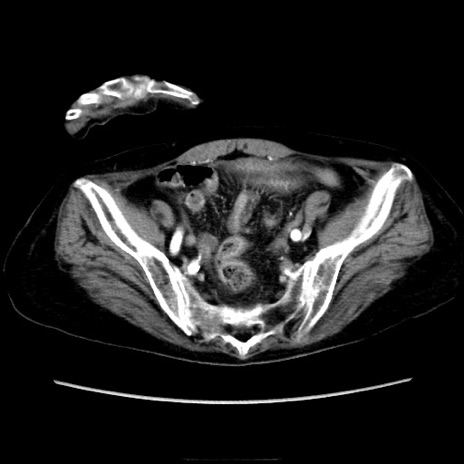

症例40(横断像)

【症例】90歳代女性

【主訴】腹痛・嘔吐

【現病歴】 食欲低下、嘔吐があり昨日他院受診。肺炎と診断され入院となる。入院後より腹部全体に圧痛あり。胃管留置され経過みていたが、症状持続するため、

当院転院となる。

【既往歴】胸椎圧迫骨折、胆石症

【身体所見】腹部:中央に激痛あり、圧痛あり、反跳痛不明

【データ】WBC 17100、CRP 18.82

横断像